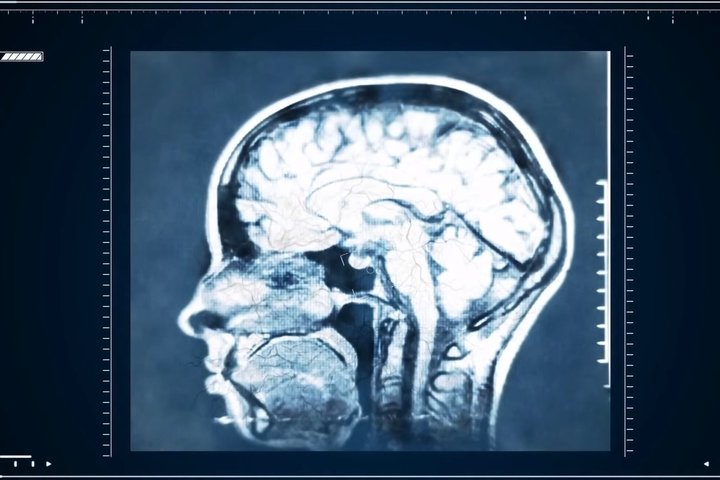

Микропластик головного мозгаКак известно, окружающая среда сегодня, в XXI веке, буквально нашпигована микропластиком: нано— и микрочастицы пластиковых материалов попадает в воздух, в воду, в продукты — и, конечно, в организм человека. Размер таких частиц варьируется от нанометра (это одна миллиардная метра) до 500 мкм (микрометр — одна миллионная часть метра). Ученые давно пытаются понять, как микропластик накапливается в организме человека. Обычно его искали с помощью микроскопической спектроскопии — и находили в легких, кишечнике, плаценте. Однако это были частицы довольно крупного размера — больше 5 мкм. Мелкий микропластик оставался невидимым.

Ученые из фармацевтического колледжа Университета Нью-Мексико (США) попробовали более чувствительные методы — пиролизную хромато-масс-спектрометрию, а еще — инфракрасную спектроскопию с преобразованием Фурье. Микро— и наночастицы искали в тканях печени, почек и мозга нескольких людей, которым проводили вскрытие в 2016 и в 2024 годах.

Оказалось, что в образцах мозга из лобной коры гораздо больше микропластика, чем в тканях печени и почек. Но главное — за восемь лет микропластика в тканях людей стало гораздо больше. Чемпион по количеству внутри нас — полиэтилен, в соседях у него — полипропилен, ПВХ и бутадиен-стирольный каучук. На этом ученые не остановились. Результаты за 2016 и 2024 годы сравнили с образцами тканей головного мозга периода 1997 — 2013 годов. Итог не удивил: в более поздних образцах пластика существенно больше.

Оказалось, что в образцах мозга из лобной коры гораздо больше микропластика, чем в тканях печени и почек. скриншот из видео «Невероятная наука 2. 5 Серия. "Неизвестный мозг". Документальное Кино» с канала «Star Media»Однако доподлинных выводов о влиянии микропластика на человеческий организм сделано пока не было — ученые всего мира бьются над этой задачей. Но проблема заключается в том, что невозможно набрать статистически достоверную “контрольную” группу испытуемых — людей, в тканях которых микропластика нет. А значит, не с чем сравнивать и делать выводы.

Так что пока нам просто нужно привыкнуть к мысли о том, что пока мы живем, дышим и едим, наш мозг усиленно накапливает внутри себя крошечную пластиковую пыль.